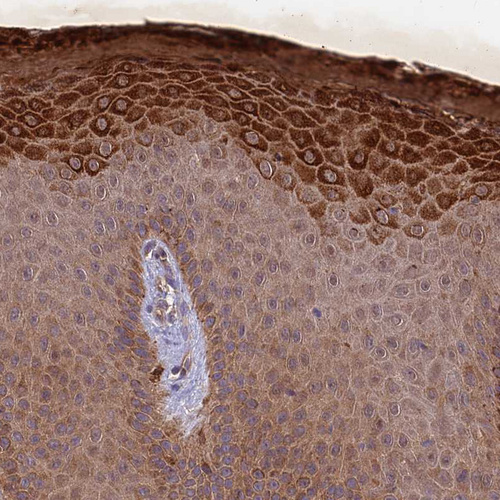

Immunohistochemical staining of human small intestine shows strong cytoplasmic positivity in glandular cells.